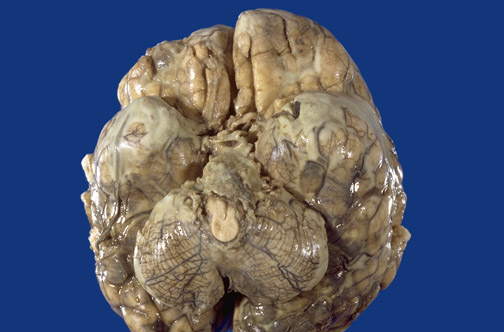

In this case of acute meningitis, the thick tan-green exudate is located at the base of the brain in a term infant.